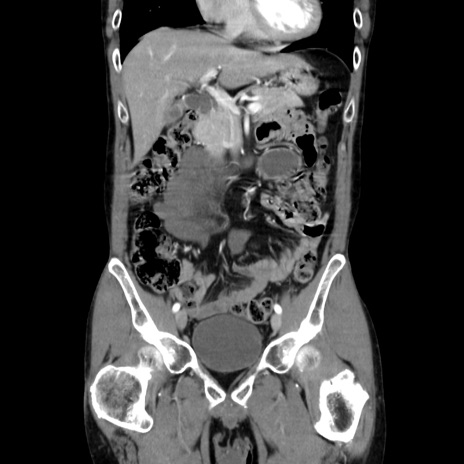

症例37(冠状断像)

【症例】40歳代 男性

【主訴】腹痛

【現病歴】4時間ほど前に電車に乗車中に臍部上より腹痛出現。徐々に増悪し起立困難となり、救急外来受診。生ものは数日食べていない。今朝お雑煮を食べた。

【身体所見】BT 36.8℃、BP 117/84mmHg、HR 91/min、SpO2 97%、苦悶様、腹部:臍上部広範囲圧痛あり、反跳痛±

【データ】WBC 8100、CRP 0.03